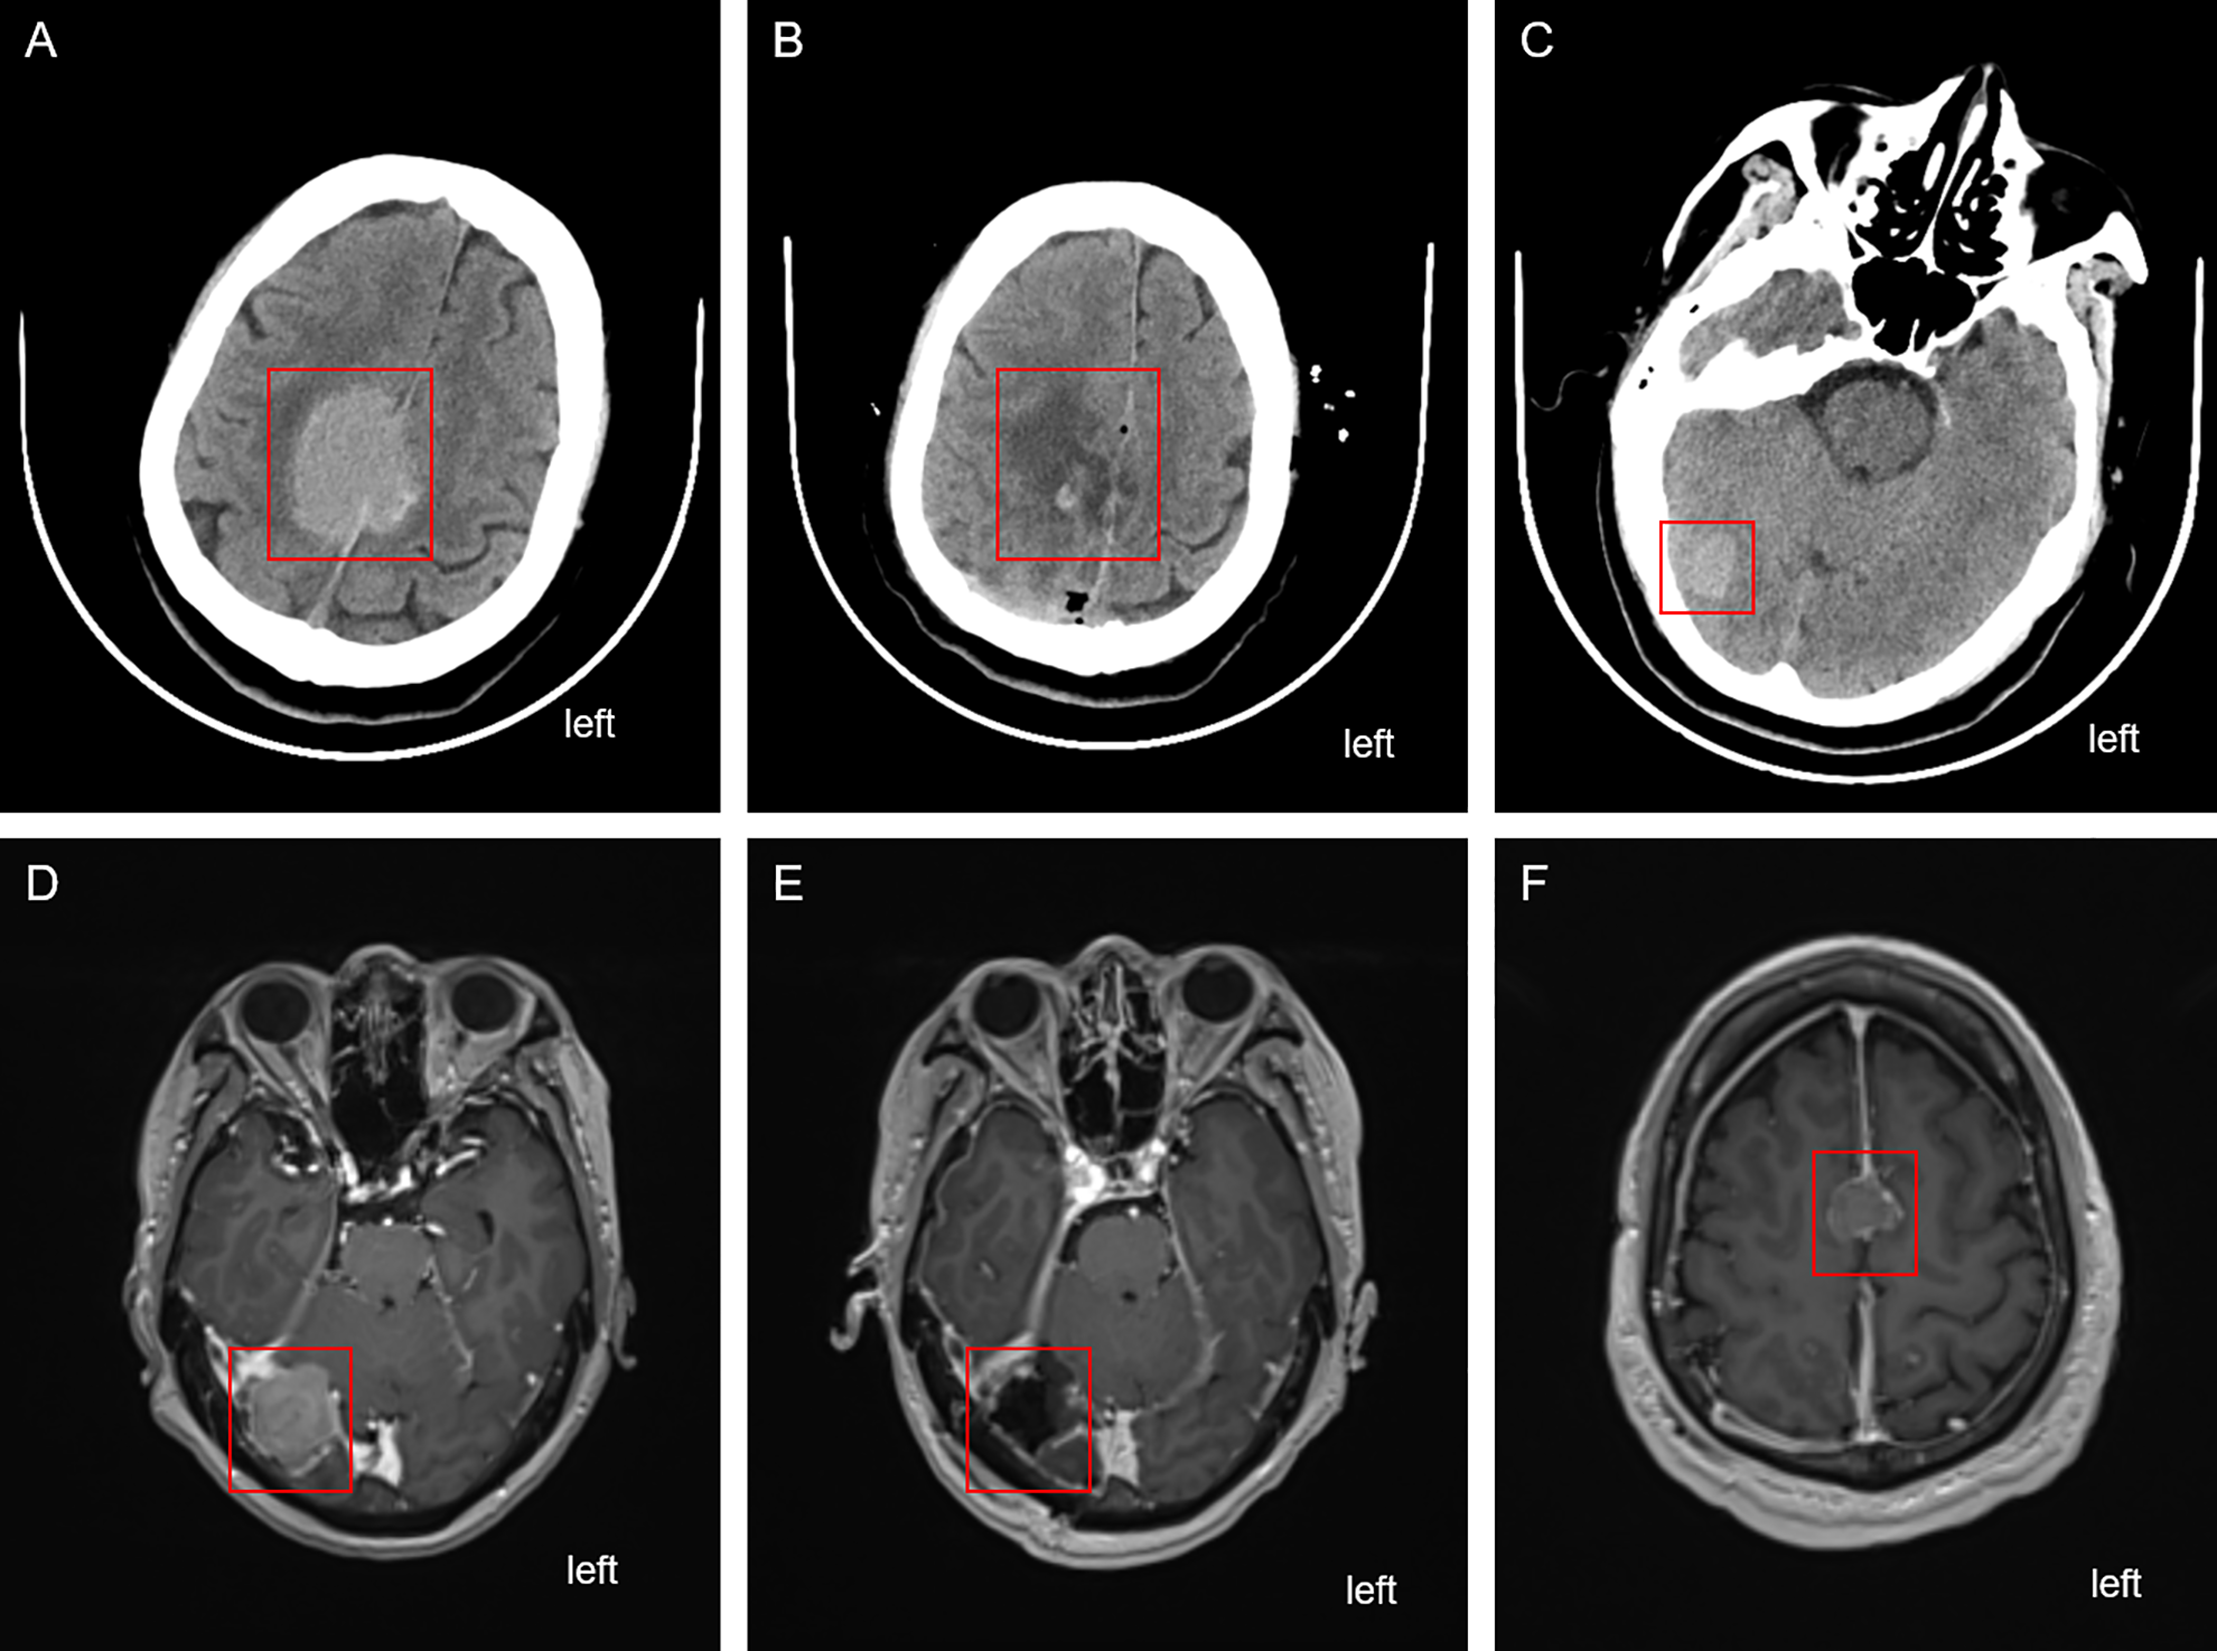

On 16 April 2024, the patient presented to the oncology clinic with a two-week history of left lower limb weakness. At that time, the PSA level of the patient was 7.858 ng/mL. Brain computed tomography (CT) revealed a round high-density lesion in the falx cerebri and a patchy high-density lesion in the right occipital lobe, both with indistinct margins (Fig. 4A). Brain MRI, including plain, contrast-enhanced, and DWI, revealed abnormal lesions in the bilateral frontoparietal falx cerebri and right occipital region. These lesions appeared isointense on T1-weighted imaging and slightly hyperintense on T2-weighted imaging, measuring approximately 4.2 cm × 3.4 cm and 1.9 cm × 1.6 cm, respectively. The surrounding brain parenchyma was compressed. The lesion exhibited mildly hyperintense signals on DWI and significant enhancement after contrast administration, with tortuous vascular shadows visible at the lesion margins. The patient was admitted to the neurosurgery department of our hospital on April 25. Considering the medical history, imaging findings, and the poor overall condition of the patient, lumbar cistern drainage and microsurgical resection of the cerebral falx lesion were performed (Fig. 4B). Due to the small size of the right occipital mass, it was not resected during the initial surgery (Fig. 4C). The pathological report of immunohistochemistry analysis revealed α-methylacyl-CoA racemase (P504S; +), PSA (+), tumor protein 63 (P63; -), high-molecular-weight cytokeratin (34βE12; -), Ki67 (~30% +), cytokeratin 20 (CK20; -), cytokeratin 7 (CK7; -), confirming that the brain tumor originated from PC (Fig. 3C). The patient recovered well postoperatively and was discharged in stable condition. At the two-month outpatient follow-up, contrast-enhanced brain MRI revealed a right occipital lobe mass enlargement, measuring approximately 38 mm × 22 mm (Fig. 4D). After informing the patient and their family about the condition and obtaining consent, a right-sided arcuate craniotomy for lesion resection was performed (Fig. 4E). Postoperative immunohistochemistry analysis revealed PSA (+), P504S (+), CK20 (−), and CK7 (-), confirming that the right occipital mass originated from PC (Fig. 3D). A recurrent tumor was also detected at the initial surgical site in the falx cerebri (Fig. 4F). However, given the compromised health condition of the patient, alternative treatment strategies were considered, and surgery was not performed. The patient was discharged in stable condition after surgery and subsequently underwent 20 sessions of whole-brain radiotherapy (WBRT) between August 5 and September 27, 2024, along with ADT maintenance, and PSA levels were maintained at a low level (Fig. 1).

Figure 4: Cranial imaging examination before and after the two brain surgeries. (A) CT scan depicting the falx cerebri tumor before the first brain surgery. (B) CT depicting the falx cerebri region after the first brain surgery. (C) Unresected tumor in the right occipital region after the first brain surgery. (D) Enhanced MRI revealing the enlarged right occipital tumor before the second brain surgery. (E) Enhanced MRI depicting the right occipital region post the second brain surgery. (F) Recurrent and unresected tumor in the frontal lobe region. The red box highlights the location of the tumor lesion